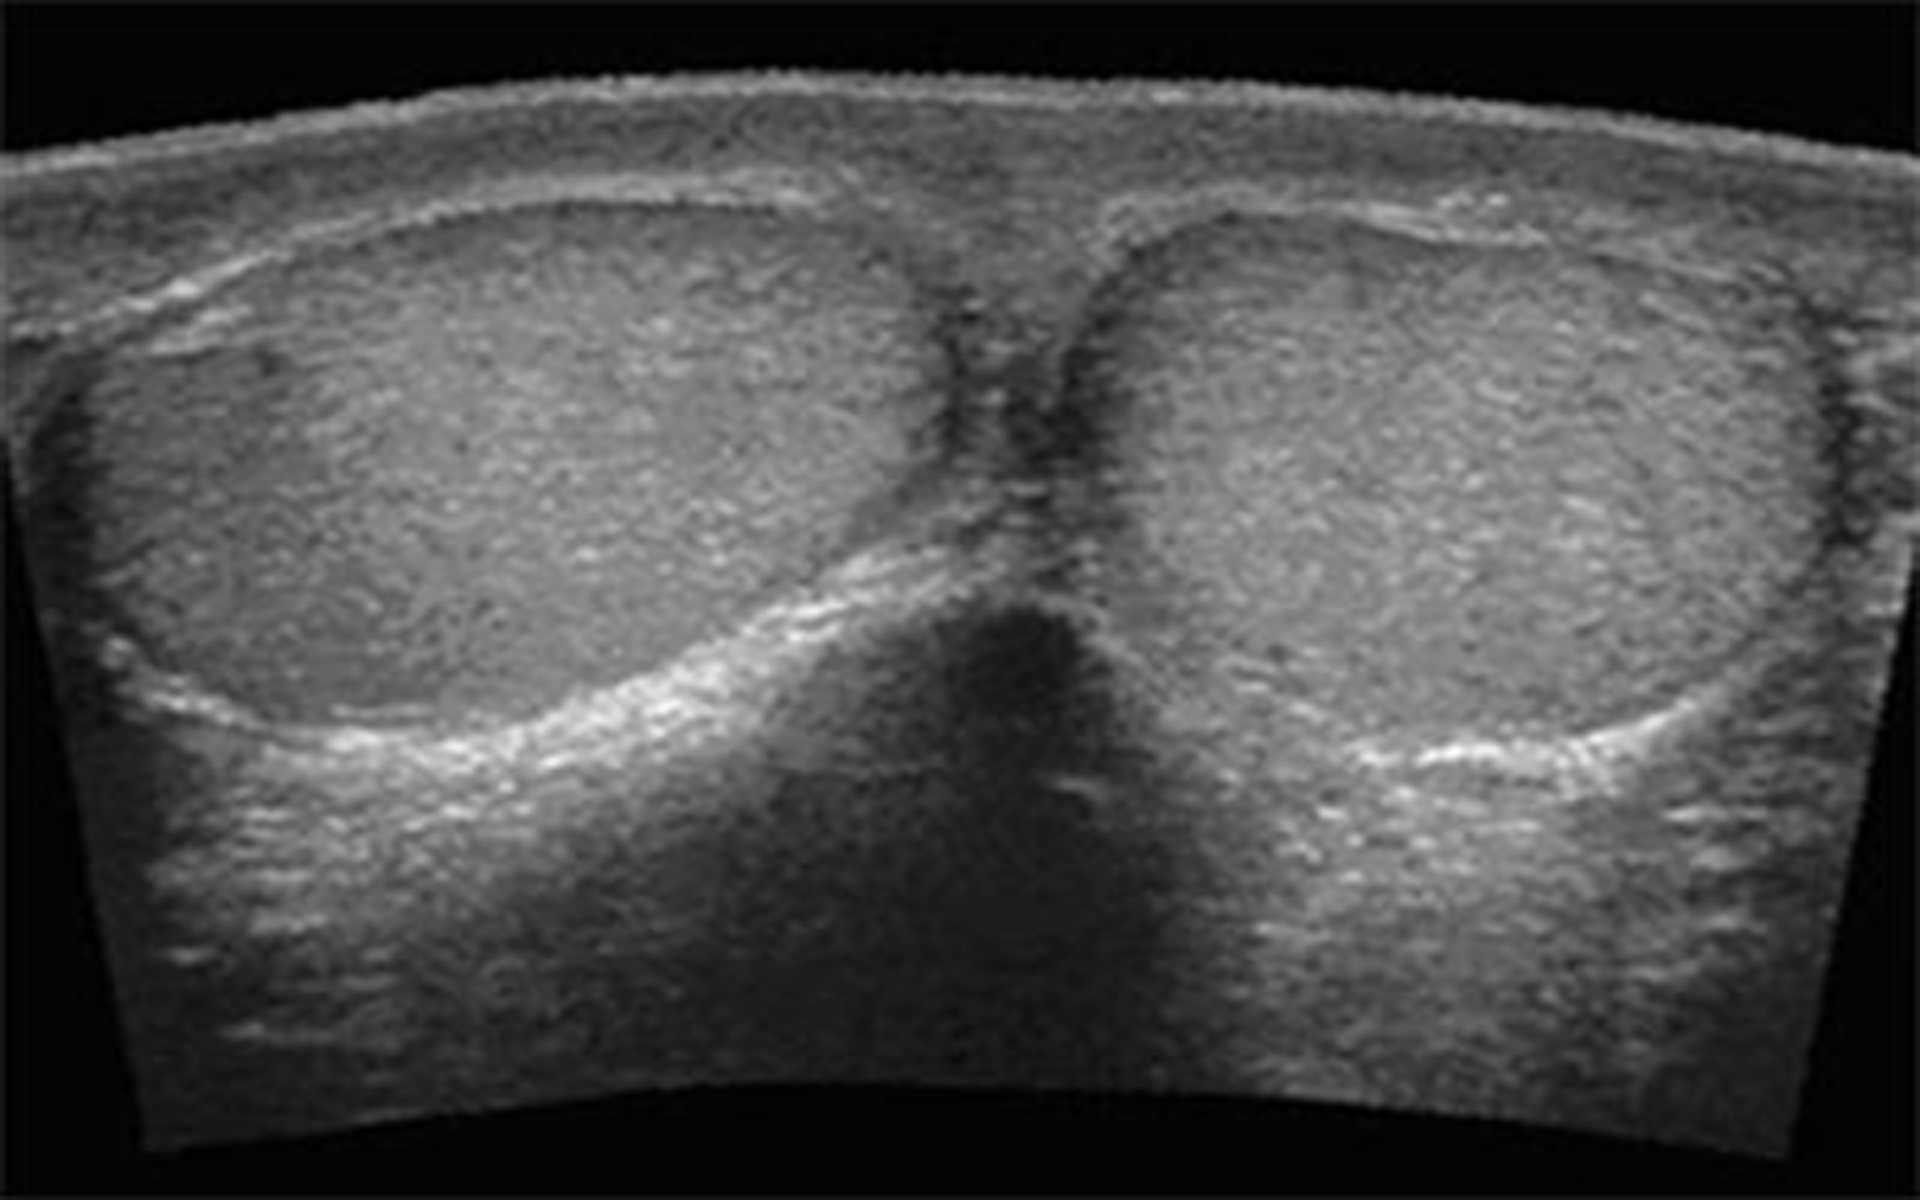

آمادگی سونو گرافی داپلر بیضه ؛ تصویربرداری اولتراسوند از امواج صوتی با فرکانس بالا برای ایجاد تصاویری از ساختارهای داخلی استفاده می کند. داپلر از بازتاب امواج صوتی ناشی از اجسام متحرک مانند گلبول های قرمز استفاده می کند. بنابراین ، سونوگرافی داپلر بیضه، ساختارهای داخلی کیسه بیضه ، عمدتاً بیضهها و جریان خون را نشان می دهد. امواج صوتی با فرکانس بالا کاملا بی خطر هستند و از امواج مضر تشعشع استفاده نمی کنند

سونوگرافی داپلر بیضه یک روش تصویربرداری تشخیصی آسان است که بیش از 30 تا 45 دقیقه طول نمی کشد. بیمار روی میز معاینه دراز می کشد، پزشک آلت تناسلی را به سمت شکم بلند می کند و کیسه بیضه را با یک ژل اولتراسوند می پوشاند (امواج صوتی با فرکانس بالا در عبور از هوا مشکل دارند) این امکان تجسم اندام های داخلی را بر روی صفحه نمایش مانیتور فراهم می کند. و ارتباط بین پوست کیسه بیضه و مبدل را تقویت می کند.

امواج صوتی از مبدل بدون ضرر از پوست عبور می کنند. یک مانیتور تلویزیون تصاویری از بیضههای شما را نشان میدهد در حالی که مبدل اکوها را به سیگنالهای الکتریکی تبدیل میکند.

ژل اولتراسوند روی کیسه بیضه بیمار قرار می گیرد و بیضه ها و اپیدیدیمیدها با پروب اولتراسوند اسکن می شوند. کلیه ها نیز در پایان معاینه اسکن می شوند زیرا گاهی اوقات آسیب شناسی بیضه می تواند به آسیب شناسی کلیه مرتبط باشد. تصاویر متعددی از سازه ها برای تجزیه و تحلیل توسط رادیولوژیست مشاور گرفته می شود. هدف ما این است که گزارش را ظرف 2 روز کاری پس از اسکن به پزشک شما تحویل دهیم.

بیضه ها، اپیدیدیم و عروق داخل کیسه بیضه ارزیابی خواهند شد. کلیه ها نیز ممکن است ارزیابی شوند.

سونوگرافی بیضه می تواند کیست های داخل اپیدیدیم، توده های بیضه و مایع داخل کیسه بیضه را شناسایی کند. سونوگرافی می تواند جریان خون در بیضه ها را ارزیابی کند و فتق روده را به بیضه ها بررسی کند.